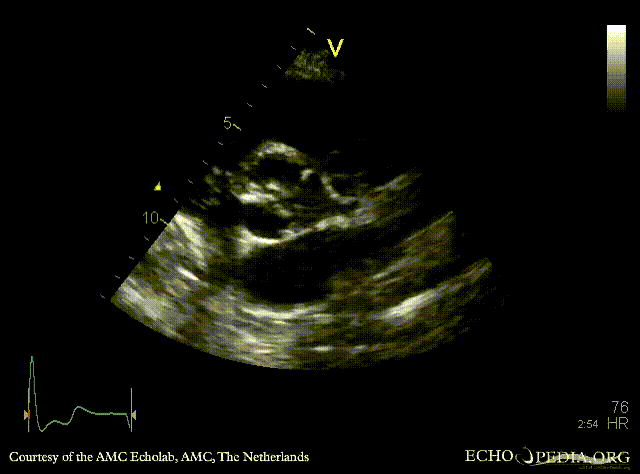

| A4CH: concentric hypertrophy of left ventricle | A3CH with Color Doppler: high velocity transaortic flow, mild aortic regurgitation |